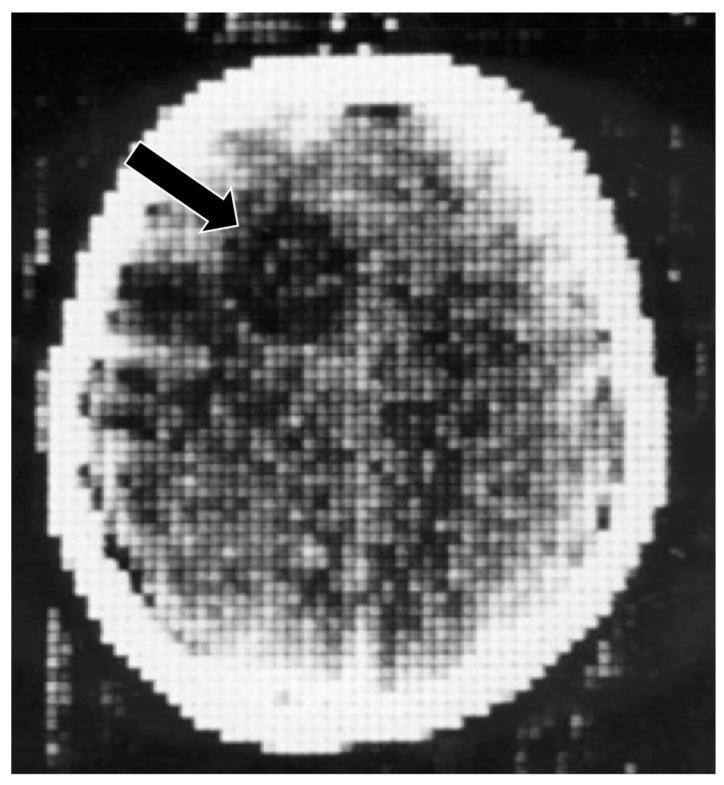

Ultra-high contrast (UHC) MRI describes forms of MRI in which little or no contrast is seen on conventional MRI images but very high contrast is seen with UHC techniques. One of these techniques uses the divided subtracted inversion recovery (dSIR) sequence, which, in modelling studies, can produce ten times the contrast of conventional inversion recovery (IR) sequences. When used in cases of mild traumatic brain injury (mTBI), the dSIR sequence frequently shows extensive abnormalities in white matter that appears normal when imaged with conventional T-fluid-attenuated IR (T-FLAIR) sequences. The changes are bilateral and symmetrical in white matter of the cerebral and cerebellar hemispheres. They partially spare the anterior and posterior central corpus callosum and peripheral white matter of the cerebral hemispheres and are described as the whiteout sign. In addition to mTBI, the whiteout sign has also been seen in methamphetamine use disorder and Grinker's myelinopathy (delayed post-hypoxic leukoencephalopathy) in the absence of abnormalities on T-FLAIR images, and is a central component of post-insult leukoencephalopathy syndromes. This paper describes the concept of ultra-high contrast MRI, the whiteout sign, the theory underlying the use of dSIR sequences and post-insult leukoencephalopathy syndromes.

超高对比(UHC)MRI 描述了这样一些 MRI 形式,在常规 MRI 图像上几乎没有或没有对比,但在 UHC 技术中可以看到非常高的对比。其中一种技术使用分裂相减反转恢复(dSIR)序列,在建模研究中,该序列可以产生比常规反转恢复(IR)序列高十倍的对比度。当用于轻度创伤性脑损伤(mTBI)时,dSIR 序列经常在白质中显示出广泛的异常,而在使用常规 T 液衰减反转恢复(T-FLAIR)序列成像时,白质看起来正常。这些变化在大脑和小脑半球的白质中是双侧对称的。它们部分保留了前中央和后中央胼胝体以及大脑半球的外周白质,被描述为“白化征”。除了 mTBI 之外,在没有 T-FLAIR 图像异常的情况下,该白化征也出现在苯丙胺使用障碍和 Grinker 髓鞘病(缺氧后迟发性白质脑病)中,是创伤后白质脑病综合征的一个核心组成部分。本文描述了超高对比 MRI、白化征、dSIR 序列使用的理论以及创伤后白质脑病综合征的概念。